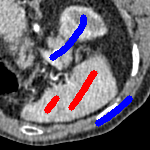

We now introduce two recent methods that incorporate user input to perform selective segmentation. Each involves input in the form of foreground/background regions to indicate relevant structures of interest. An example of this can be seen in Fig. 18, where red regions indicate foreground and blue regions indicate background. We compare against the work of Nguyen et al. Nguyen:12 , which uses a similar convex relaxation framework to the proposed approach, and Dong et al. SRW , which uses a variation of the random walk approach. We summarise the essential aspects of each approach in the following.

In order to further establish the robustness of our method, we now introduce the results of testing our approach against competing interactive segmentation methods on a larger data set. The results are presented in Fig. 17, showing a boxplot of accuracy in terms of TC on a set of 30 CT images (excluding outliers). The target structure we consider is the spleen, as this consists of a relatively homogeneous foreground, appropriate for the approach considered. The data has been manually contoured providing ground truth data for the image set. We compare CAC Nguyen:12 and SRW SRW against our method with five variations of user input for each image. It is worth emphasising here that the input used in the tests is identical for each approach and was not refined in any way. It was designed to mimic what a user, unfamiliar with each approach, might select intuitively. A representative example for three images is shown in Fig. 18. This shows foreground (red) and background (blue) user input regions. For our method, we define the red region as as discussed in §1 and enforce hard constraints on the blue region. We refer to the results of the proposed approach using this input as Ours (i). We also include results of randomising the user input in an identical way to §7.3. For each image we generate 1000 simulated user input choices, which we present as Ours (ii). It is important to note that the difference between Ours (i) and (ii) is only the definition of . The method and parameters are fixed between each.